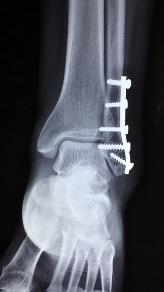

발목 퇴행성 관절염은 발목의 연골과 인대가 부서지거나 마모되어 발생하는 만성적인 관절염입니다. 이 질환은 노화, 스포츠 손상, 다양한 병리적인 원인 등으로 인해 발생합니다. 이 질환은 일반적인 발목염과 달리 연령이 들어갈수록 증상이 악화되어 조작이 어려워지고 일상생활에도 지장을 주는 경우가 많습니다. 발목 퇴행성 관절염의 증상에는 발목통, 경직, 염증, 관절의 강직성, 가동범위 제한 등이 포함됩니다. 이러한 증상은 보통 시간이 지남에 따라 악화됩니다. 적절한 치료 없이 지속되면, 발목 퇴행성 관절염은 관절염증, 연골 손상, 영구적인 관절 손상 등을 유발할 수 있습니다. 적절한 관리와 치료를 통해 증상을 완화시키고, 관절의 기능을 유지하는 것이 중요합니다.